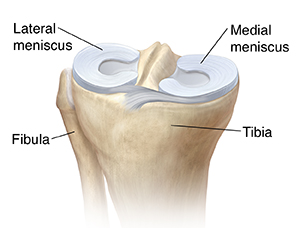

The meniscus is a tough cushion of fibrous tissue called cartilage in the knee joint. It cushions the knee. It absorbs shock and helps spread weight across the knee joint. It also works with other parts of the knee to help keep the joint stable. Injury or aging can cause the meniscus to tear and lead to pain and problems using the knee.